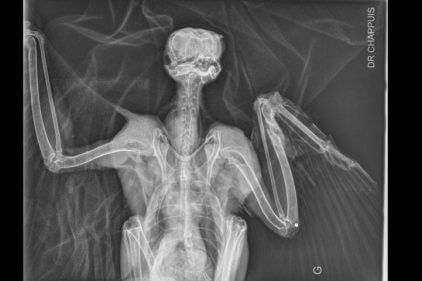

L’impression 3D au secours des oiseaux

Les progrès technologiques sont parfois bénéfiques pour la nature. Exemple avec la LPO Auvergne qui innove pour soigner les oiseaux.